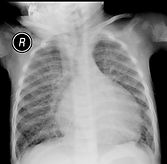

This eight year old boy complains of headache, lasting for last 3 months. No history of trauma. CNS exam including fundus was normal. Locallized tenderness noticed on the parietal side. No swelling. CT skull is enclosed

1. Radiological finding

2. Probable clinical dx?

3. Pathophysiology?

4. Specific Microscopic (EM) findings